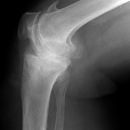

Kniegelenk